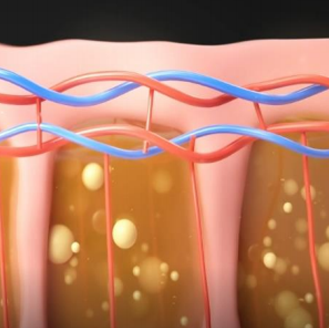

심부볼은 볼 안쪽 깊숙이 위치한 지방 덩어리로

피하지방과는 달리 다이어트로는 빠지지 않는 고유한 구조물입니다.

볼 안쪽 깊은 곳에 위치

다이어트로 빠지지 않는 지방